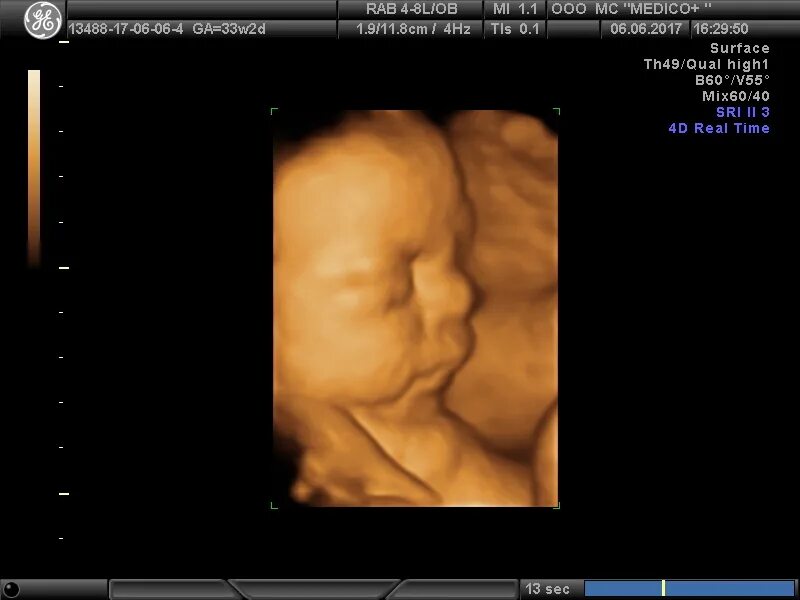

Плод 33